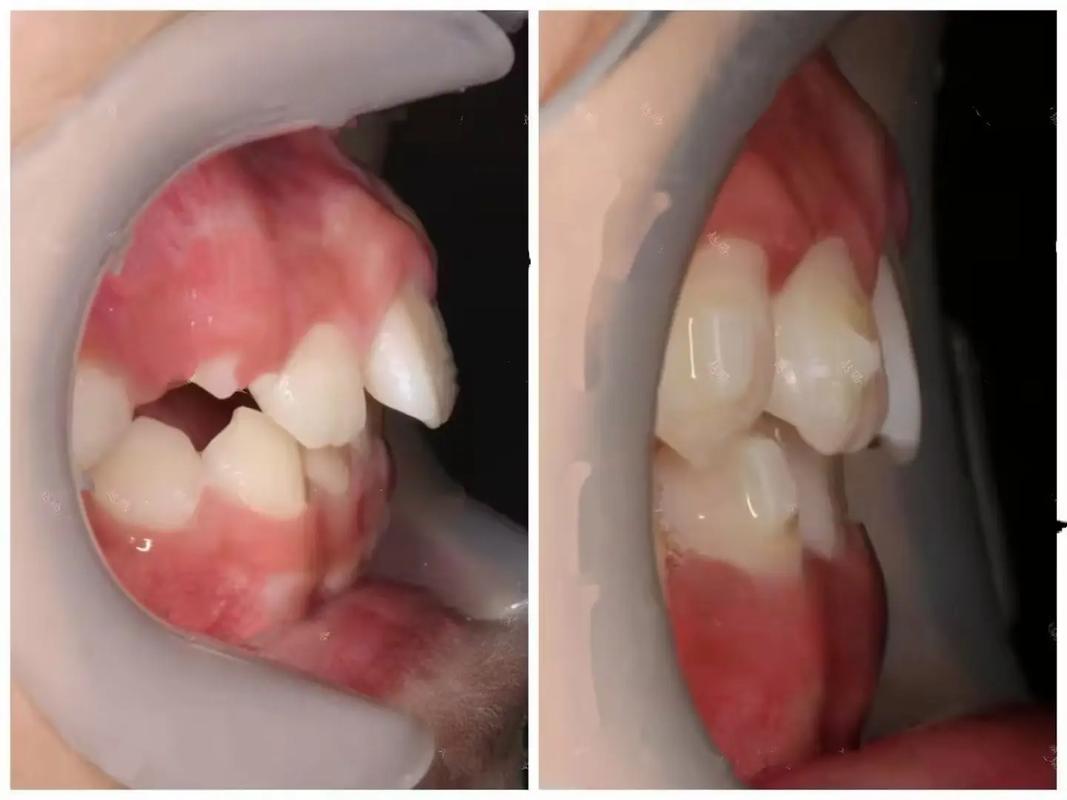

- 牙齿前凸(龅牙)矫正:内收前牙后,嘴唇会从“突出”变为自然贴合,侧脸线条从“月牙形”变为流畅的“直面型”,视觉上改善凸嘴导致的“土气感”。

矫正初期(前3-6个月),牙齿开始移动但牙槽骨改建尚未完成,唇部、颊部肌肉会因牙齿位置改变出现暂时性“不适应”。

- 嘴唇变“瘪”:前牙内收过快时,唇部软组织失去牙齿支撑,可能暂时显得凹陷,尤其是原本嘴唇较薄者;

- 脸颊凹陷:拔牙矫正后,牙齿向拔牙隙移动,颊部可能暂时性“塌陷”,待牙槽骨稳定后会逐渐恢复;